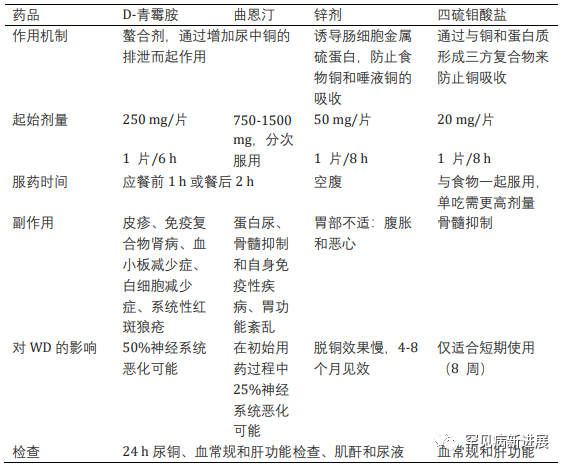

病例情况 病例一:伴有帕金森症状的共济失调型;病例二:伴有帕金森症状的肌张力障碍。两名患者均接受裂隙灯检查有 K-F 环(图1)。 肝脏超声检查有明显结构异常,实验室检查肝功能正常,低血清铜、低铜蓝蛋白和尿铜排泄增加,均无基因检测。(表一) 据统计50% 的肝脏和 99% 的神经系统病变患者有K-F 环(后弹力膜上铜沉积)。 表2: 第8届WD国际会议诊断标准(Leipzig评分) 注:总分≥4分可确诊;总分3分为疑似诊断,需进一步检查;总分≤2分基本不考虑诊断;a:肝铜定量不可及时;ULN:正常值上限 脑部磁共振成像未显示典型的双熊猫征,但在壳核、尾状核和丘脑核上显示对称的 T2/FLAIR 高信号(图 2和图 3)。 两案例均高度暗示了矿物沉积,根据 Leipzig评分,均是 WD 的明确案例。 案例 1 的T2加权序列的代表性图像。背侧区域有高信号B.上中脑轴向切开;中脑被盖上有汇合的高信号C.外侧裂轴向切开;外侧丘脑、尾状核和壳核区有明显的高信号D.岛状区轴向切开;在丘脑和基底神经节可见广泛的双侧高信号E. Corona radiata 轴向切割;双侧半卵圆形未出现任何信号异常 案例 2 的T2加权序列的代表性图像。脑桥背侧区域有高信号B.上中脑轴向切开;黑质C区有外观正常的红色核高信号。壳核上有明显的高信号,有磁化率伪影区域,左侧多于右侧D.侧脑室区域轴向切割,壳核和尾状核上可见连续广泛的高信号E.冠状放射状轴向切割,双侧半卵圆形未见任何信号异常。 由于这种疾病的罕见性,启动基于人群的筛查并不具有成本效益。但对于无法解释的神经系统疾病伴或不伴相关肝病的患者,筛查应该强制性。WD 须与诸如特发性震颤、年轻发病的帕金森病、全身性肌张力障碍和其他罕见的运动障碍(如亨廷顿病、Hallervorden-Spatz 病、特发性扭转性肌张力障碍、舞蹈病-棘红细胞增多症和良性家族性舞蹈病)区分开来。因此,WD 是一种诊断紧急情况,需要立即全面检查。 管理 至于治疗,明确的治疗包括肝移植,特别是对于急性肝炎或暴发性肝功能衰竭的患者。对严重和神经系统后遗症患者,最好的选择是直接增加尿中铜的排泄,即 D-青霉胺和曲恩汀,或阻断胃肠道对铜的吸收,即锌剂和四硫代钼酸盐(表三)。低铜饮食是主要的治疗方法,并补充锌,随后注意到言语、震颤和四肢僵硬的显著改善。第一个病例接受了 D-青霉胺治疗,药物输注缓慢以减少血液不良后果并监测反常的神经功能恶化。至于第二个病例,由于基线神经系统状态相对严重且恶化风险高,该患者继续服用锌补充剂。因无两个相同 WD 患者,治疗应个体化。对螯合剂和药物治疗无效的衰弱性运动障碍患者,可提供肉毒杆菌毒素注射。筛查患者的兄弟姐妹并监测他们的血清铜蓝蛋白也是管理的重要组成部分。早期干预有更好预后,治疗应紧迫。 表三